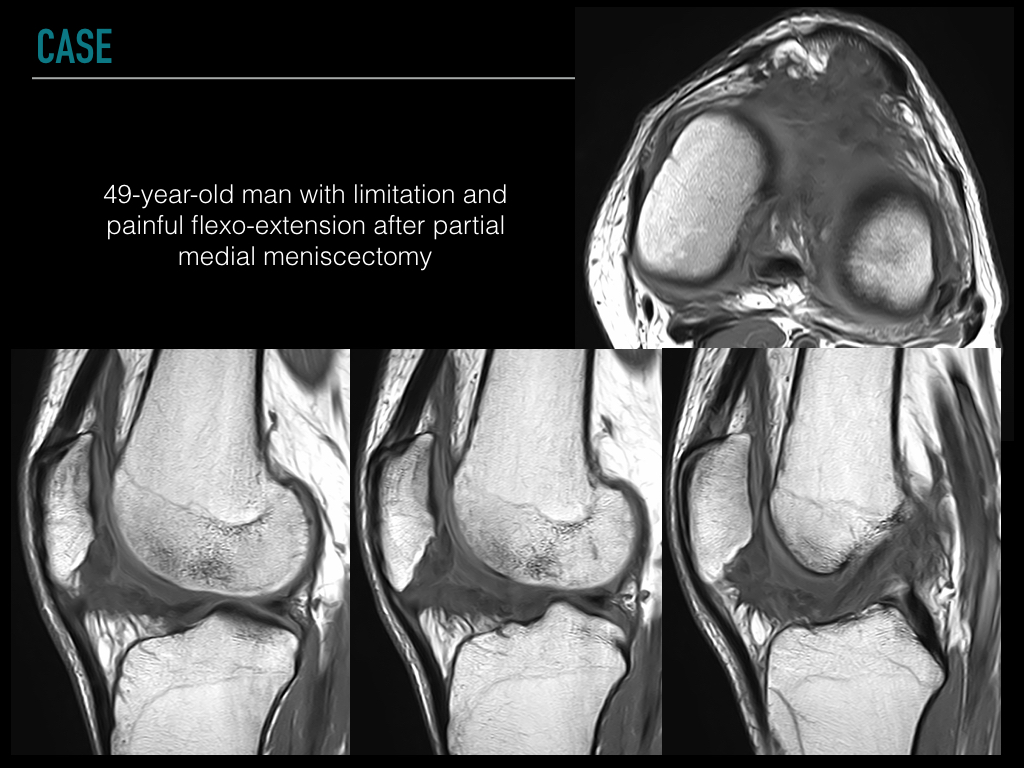

49-year-old man with limitation and painful flexo-extension after partial medial meniscectomy

At MR imaging, generalized arthrofibrosis is seen extending into the infrapatellar fat pad, suprapatellar recess and the posterior joint capsule. Thickening of the sinovial plicas and intraarticular fibrous bands are also common findings.